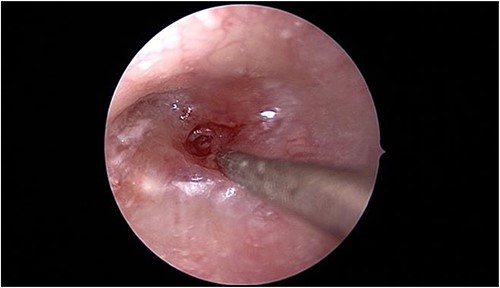

In view of the findings, the patient was taken to the operating room for left tympanomastoidectomy with bilateral tympanostomy tubes insertion and intraoral drainage of the left BA. Intraoperatively, the left tympanic membrane was already healed; however, it was significantly thickened and inflamed during myringotomy. The middle ear space was full of granulation tissue with no purulent discharge that could be retrieved (Fig. 3).

Intraoperative endoscopic view of the left middle ear cavity filled with granulation tissue.

The mastoid bone had no bony erosion of the septations. There was only granulation tissue in the antrum, sigmoid sinus area and the tip air cells. Also, necrotic tissue at the tip of the mastoid was noticed. The sigmoid sinus was partially dehiscent covered with granulation tissue. Similarly, inflammation and granulation were seen while performing the right myringotomy. The left parapharyngeal abscess was drained using an 18-gauge needle aspiration followed by a small incision and thorough irrigation of the abscess.